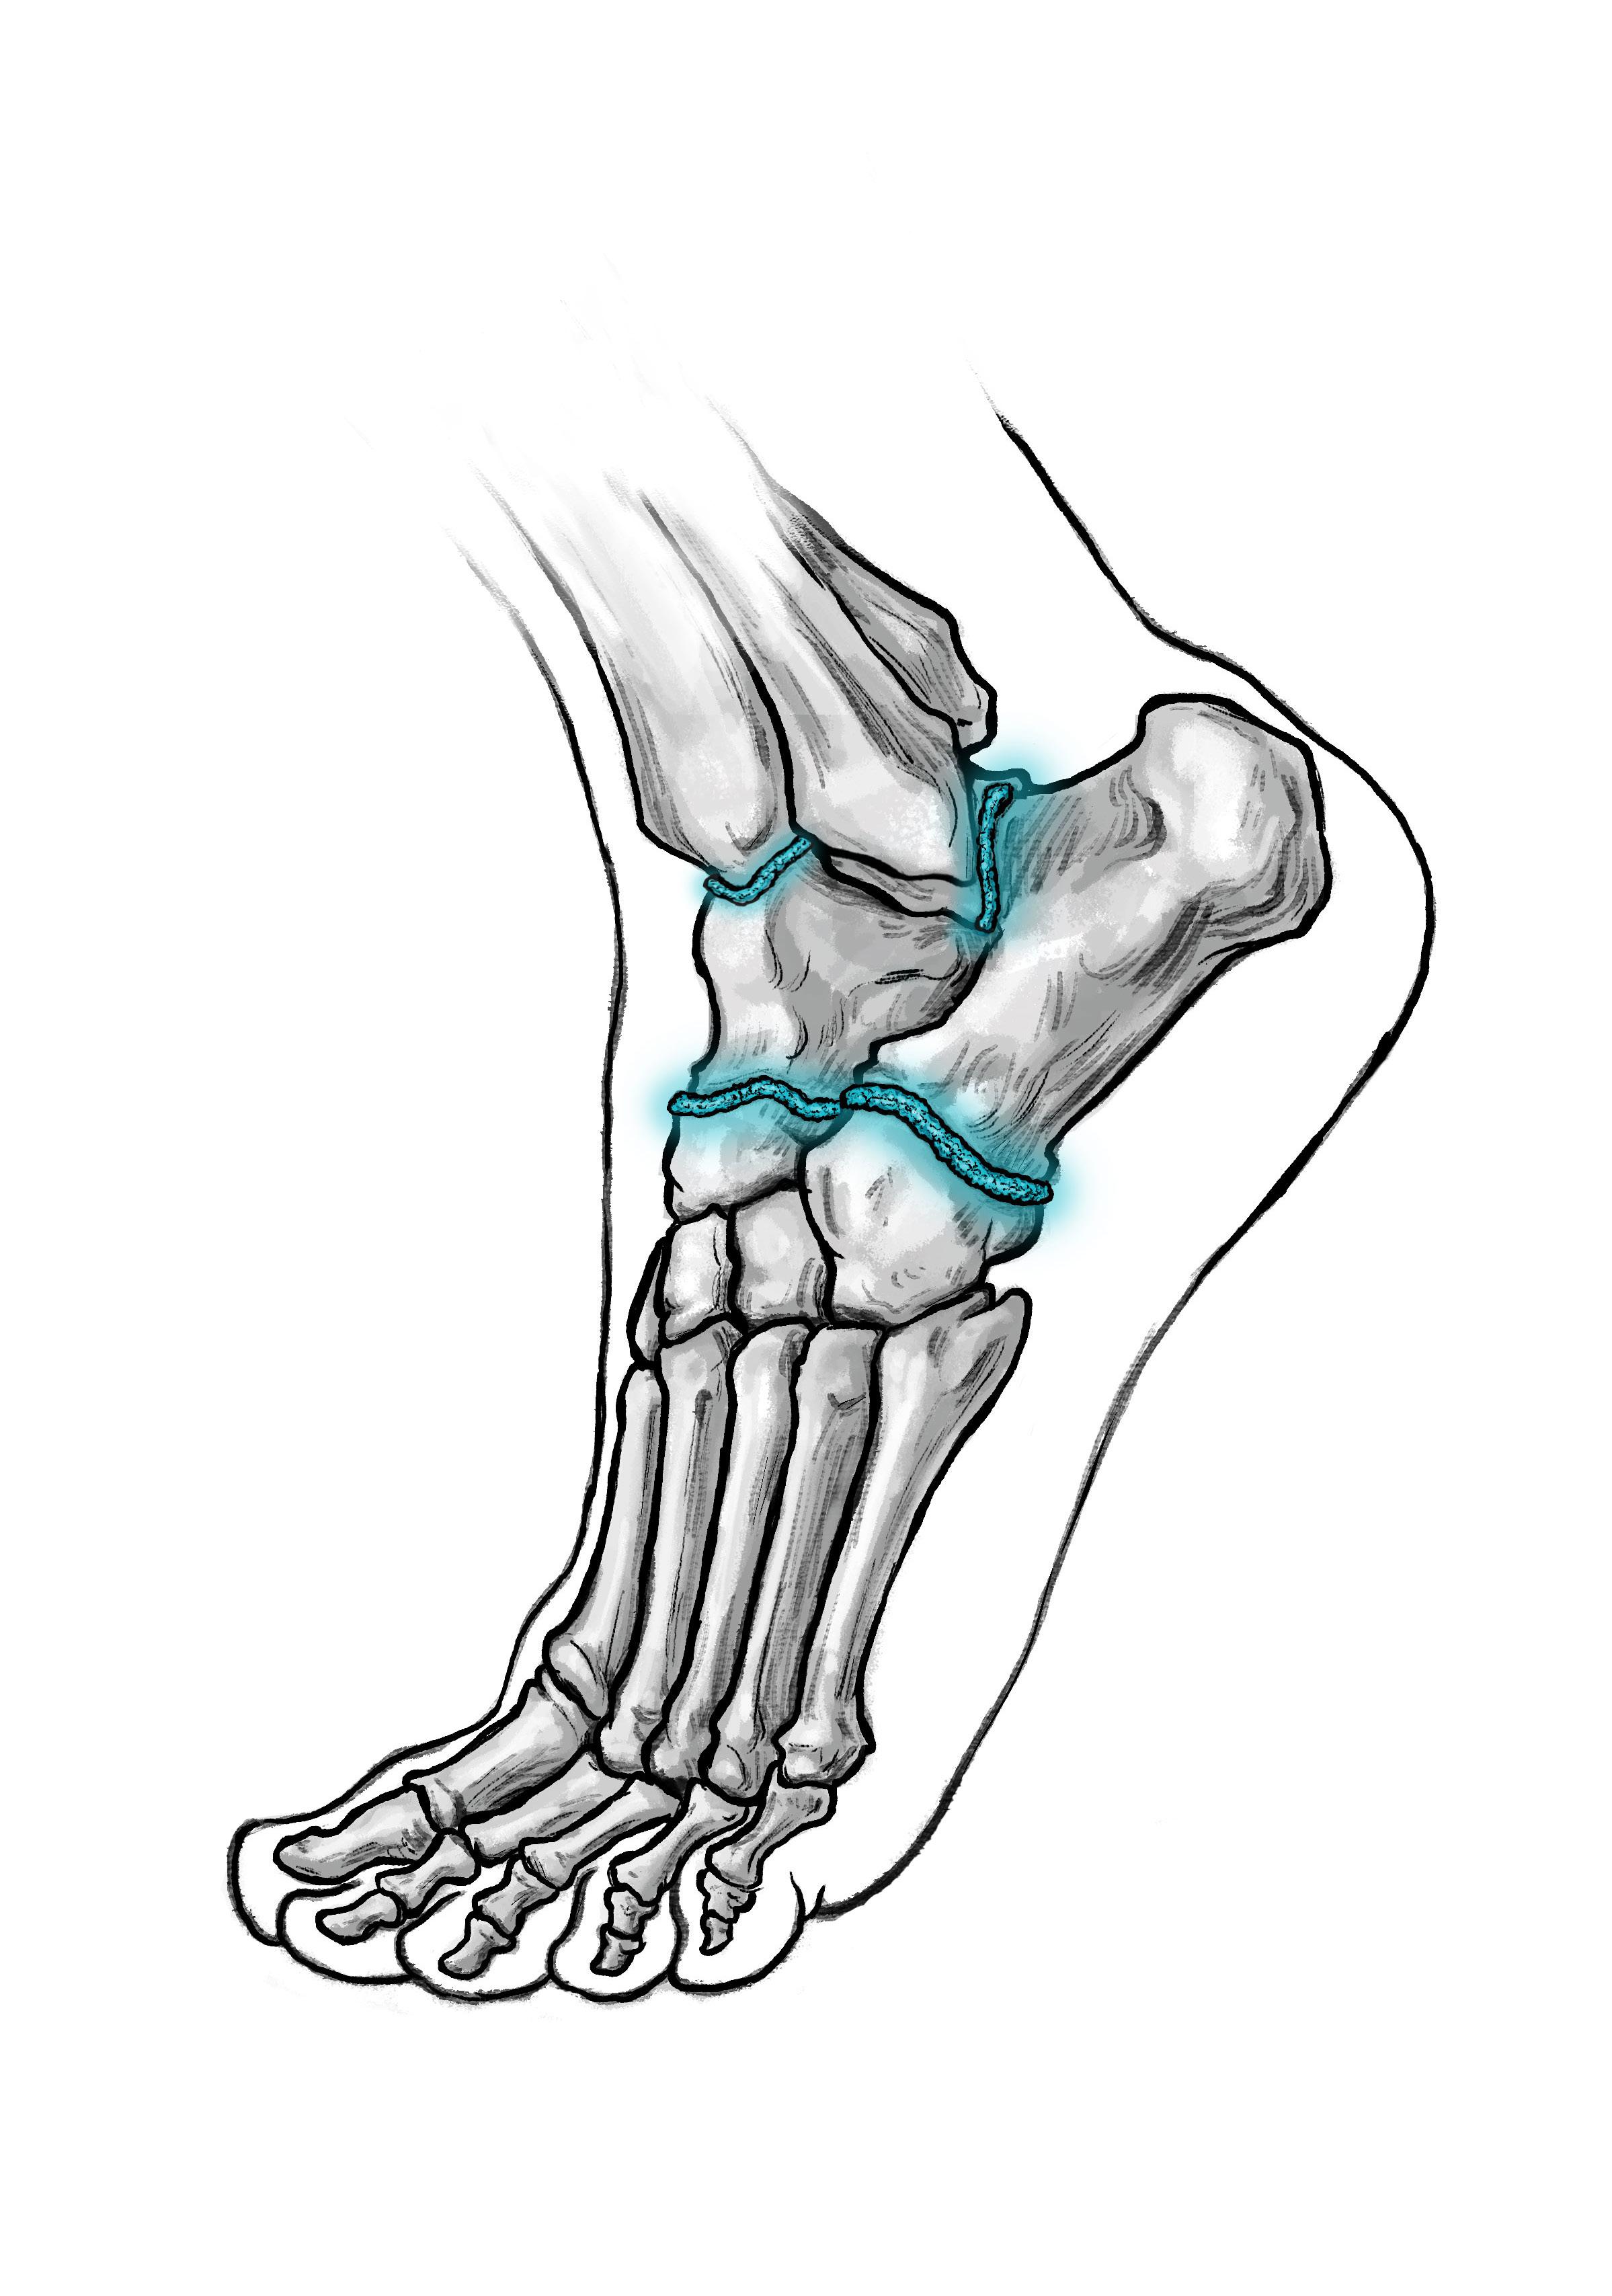

Posterior malleolar fractures (PMFs) account for up to 50% of ankle fractures when assessed with CT. The historical “one-third rule” guided fixation by fragment size; however, morphology and stability are now recognised as more important determinants of outcome.

Surgical fixation of PMFs is commonplace in unstable and displaced fracture patterns. Having spent the last decade researching PMFs, one of the most significant findings has been the importance of the correct surgical approach. Although the posterolateral (PL) approach remains common, in my practice it has been completely abandoned. Increasing evidence supports the medial posteromedial (MPM) approach in the exposure and fixation of PMFs, which has substantial benefits over the PL approach.

I will discuss these advantages of the MPM over the PL approach in the following article.

what is the mPm Approach?

The MPM approach gains access to the posterior and medial aspect of the tibia. Figure 1 illustrates these steps on a cadaveric specimen. The skin incision is marked out 1cm posterior to the posteromedial edge of the tibia and can be extended anteriorly along the path of the posterior tibial tendon (PTT) if access to the anterior aspect of the medial tibia is required. The investing layer of fascia is opened longitudinally exposing the sheath to the PTT and separately the flexor digitorum longus tendon (FDL) sheath. The PTT and FDL sheaths are opened (although keeping the distal aspect intact) and access to the posterolateral tibia is gained between the PTT and FDL and the posteromedial tibia in front of the PTT.

Advantages of the mPm Approach over the PL Approach

1. Superior Exposure

The MPM approach allows good visualisation of the posterolateral,

posteromedial and medial (with anterior extension) aspect of the tibia. In comparison the PL approach allows access to a small aspect of the posterolateral tibia and the fibular (figure 2). Direct comparison of the exposures has shown almost double the surface area exposed by the MPM as compared to the PL1.

2. Soft-tissue Entrapment Clearance

PTT entrapment has been found in over 40% of PMFs when the fracture line enters the PTT sheath2. In the MPM approach, the PTT sheath is visualised, entrapment can be identified and released. With the PL approach, this is not possible.

3. Access to Die-Punch Fragments

Die-punch injuries are common in PMFs and most frequently occur under the posterolateral fragment. The MPM approach allows direct access to the die punch fragment, when the PL does not. It is easier to go through the open door than the hinge.

4. Vascular Safety

Vascular studies have shown two important aspects regarding the risks posed by the PL approach3. Firstly, the flexor hallucis longus (FHL) muscle is supplied by up to six perforators from the peroneal artery. By moving the FHL medially to get access to the posterior tibia during the PL approach, the FHL is moved away from the peroneal artery and can therefore lose its blood supply and become necrotic. If you have seen a FHL contracture following a PMF fixation, this is the reason.

Lyndon Mason Consultant, NHS University Hospitals of Liverpool Group; Honorary Associate Professor, University of Liverpool

The risk increases, the longer the incision. Secondly, and more importantly, in a twovessel limb (dominant peroneal artery and anterior tibial), the blood supply to the foot is supplied by a communicating vessel connecting the peroneal and tibial arteries (figure 3). This communicating branch is very commonly sacrificed in the PL approach If this is sacrificed in a two vessel limb, this can result in an avascular foot4. The MPM comes anterior to the FHL and communicating branch and does not have these risks.

5. Positioning and Practicality

The MPM approach can be performed in a supine, semi-prone or prone position (figure 4). This simplifyss anaesthesia, allowing easier fluoroscopy and access to the anterior tibia if required. and enabling simultaneous fibular or syndesmotic fixation.

6. Fibular fixation

Often the PL approach has been chosen due to the simultaneous access to the fibular. However, except for simple fractures, this can be problematic. In cases with high fibular fractures, anterior syndesmosis injury and significant shortening, it is technically less demanding to do a MPM approach with a supplementary direct lateral approach.

7. Revision procedures

Like in the case of die punch injuries, the MPM allows much easier access to the joint. This is achieved by hinging the PMF on the posterior inferior tibiofibular ligament. The PL approach only allows access from superior to inferior, therefore the incision has to be long.

8. Allows extension

The MPM approach is on the medial fasciotomy line and can therefore be extended as far as the knee. In contrast, the PL approach is crossed by the sural nerve, multiple muscles and the peroneal artery.

Clinical and radiological Outcomes

Recent CT-based studies have reported >90 % anatomical reduction within >>

“The mpm approach allows good visualisa T ion of T he pos T erola T eral, pos T eromedial and medial aspec T of T he

Figure 2: Schematic diagram showing access to the tibia form either the PL or MPM approach.

Figure 1: Surgical steps of the MPM approach, with the last picture illustrating the anterior extension allowing access to the medial tibia.

2mm and >90 % syndesmotic congruity after MPM fixation, however other studies using PL approach only achieve approximately 50% anatomical reduction5, 6 Our own data has shown complication rates up to 66% following PL fixation, compared with 8% using MPM when using the Clavien-Dido classification for complications.

discussion

The MPM approach overcomes the three principal limitations of PL approach, restricted exposure, unaddressed entrapment, and vascular risk. Its direct vision of the posterior and medial tibia enables true anatomical reduction, particularly in die-punch and 2B PMFs. The ability to clear PTT entrapment prevents secondary displacement and pain. Preservation of the posterior vasculature markedly decreases complication rates. Adoption requires anatomical familiarity, but reproducibility and outcomes justify its broader implementation. In my view, due the vascular risks of the PL approach specific to a two-vessel limb, continued use of the PL approach should instigate a CT angiogram pre-surgery.

Conclusion

The MPM approach provides:

• Comprehensive exposure of the posterior and medial tibia.

• Effective clearance of posterior tibial tendon entrapment.

• Direct management of die-punch fragments.

• Superior vascular safety compared with posterolateral dissection.

Across anatomical, biomechanical, and clinical domains, the MPM approach is showing safer and more accurate fixation than PL. It should be considered the preferred exposure for most posterior malleolar fractures with medial or central involvement. n